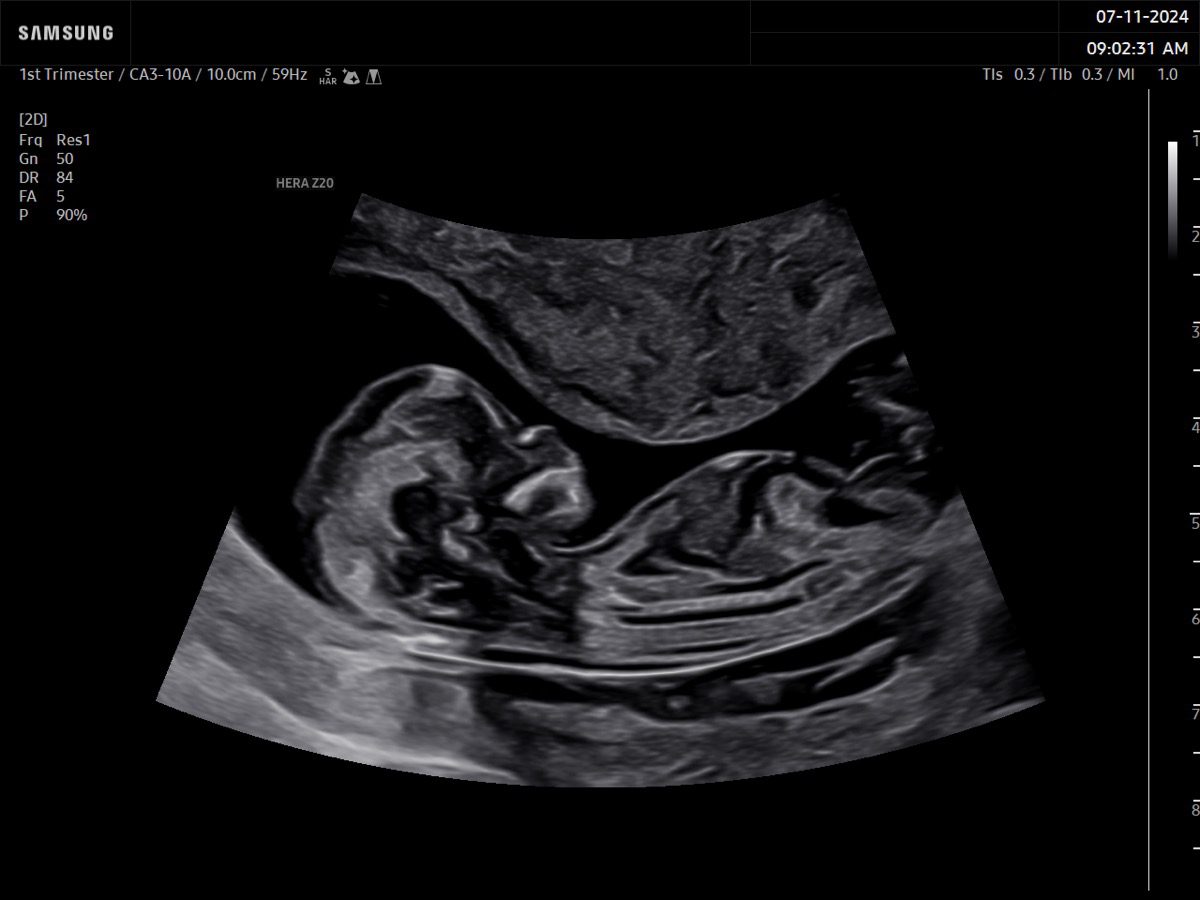

Comprehensive, advanced and expert MFM care for high-risk pregnancies

- Fetal anomalies